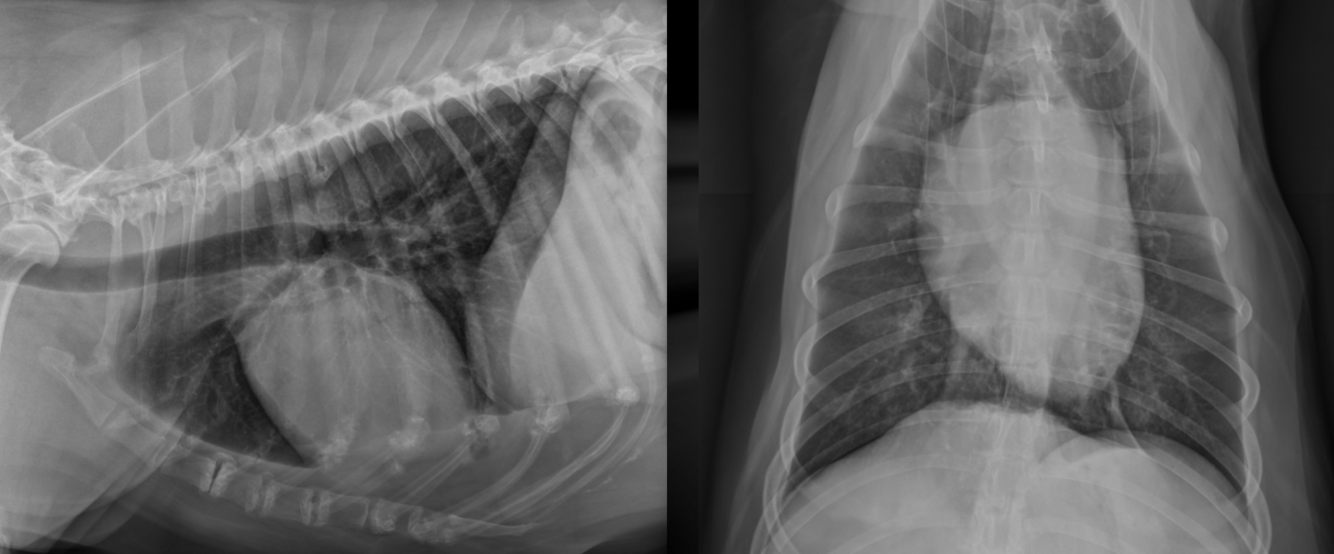

What is important regarding the ribs in these radiographs?

young dog; costal cartilages have not mineralized at all

middle-aged dog; costal cartilages have mineralized but not excessively